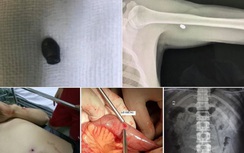

Theo một nguồn tin, bé gái bị nhiều nhát chém khiến dạ dày, phổi, gan đều bị thủng. Ngoài ra, bé cùng phải chịu nhiều vết chém khác trên người. Hiện bé đang nguy kịch tại bệnh viện. Còn mẹ của bé đã tỉnh nhưng chưa thể nói được.